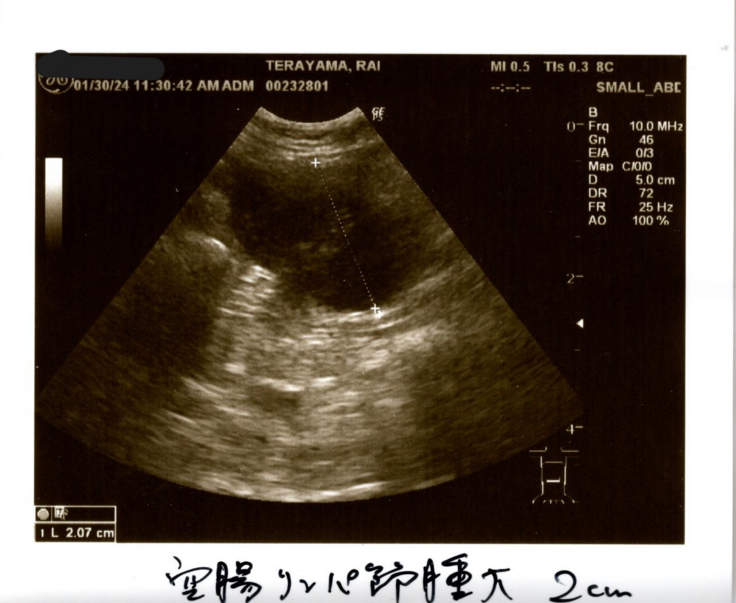

②空腸リンパ節腫大→腹腔内のリンパ節が腫れている